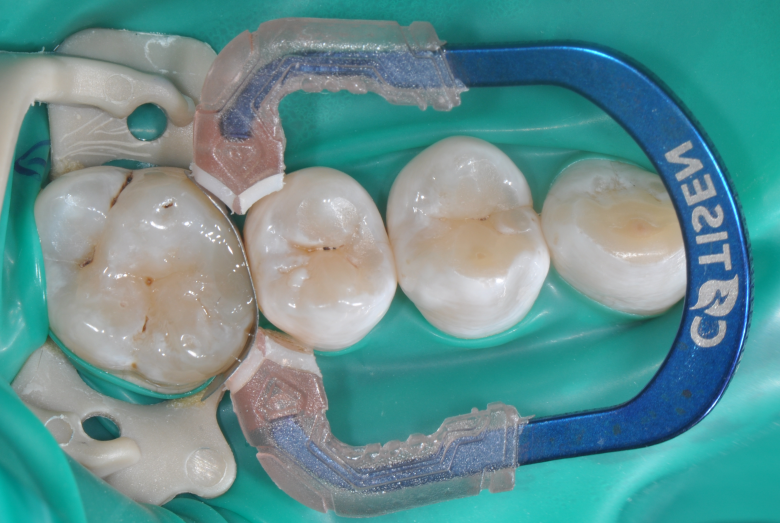

牙医-马小寒【实操病例】

右上6号牙位的近中,可见隐约龋坏

◆去腐完成之后

在以树脂充填为前提的案例中,无需过度制作颌面的鸠尾固位型,橡皮障下隔湿,是临床粘结操作技术成功的重要保障。酸蚀剂在使用的时候,需要尽量避免对邻牙的伤害